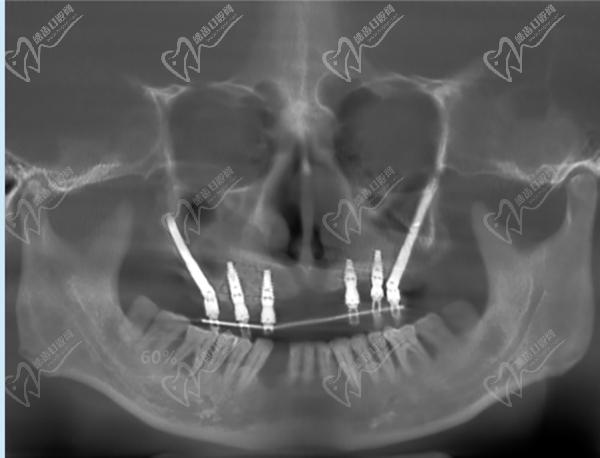

半口種植牙·集采種牙:21860元起

全口種植牙·集采:42720元起

廣州黃埔區(qū)種植牙半口牙多少錢(qián)?21860元起~6萬(wàn)元起

半口即刻負(fù)重種植牙:4萬(wàn)元起

廣州黃埔區(qū)全口種植牙價(jià)格表:42720元起~14萬(wàn)元起

全口種植牙·集采種牙:42720元起

全口即刻負(fù)重種植牙:8萬(wàn)元起